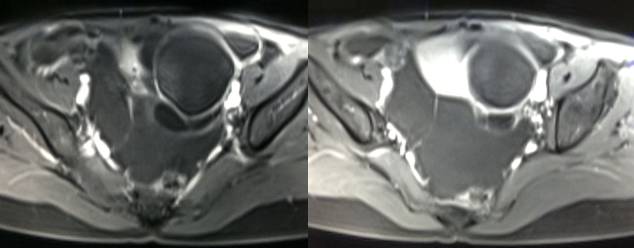

MR检查:

病理结果:黄体血肿

黄体血肿为正常排卵过程中,卵泡层破裂,引起出血,较多的血液潴留在卵泡或黄体腔内形成血肿。

正常黄体直径为15mm左右,以后转变为白体,并在下一个周期的卵泡期自然消退。若黄体内出血量较多,则形成黄体血肿,或称黄体内出血,出血性黄体。黄体血肿多为单侧,一般直径为40mm,偶可达100mm,黄体血肿被吸收后可导致黄体囊肿,较大的血肿破裂时可出现腹腔内出血,剧烈腹痛、少量阴道流血和腹膜刺激征,不易与宫外孕区别。

根据时间不同MR信号也有所不同,TIWI脂肪抑制序列可以鉴别脂肪和出血。